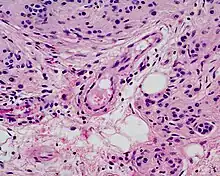

Deep congenital nevus

Microscopically, congenital melanocytic nevi appear similar to acquired nevi with two notable exceptions. For the congenital nevus, the neval cells are found deeper into the dermis. Also, the deeper nevus cells can be found along with neurovascular bundles, with both surrounding hair follicles, sebaceous glands, and subcutaneous fat. Such annexes and the Subcutaneous tissue can also be hypoplasic or, conversely, present aspects of hamartoma.